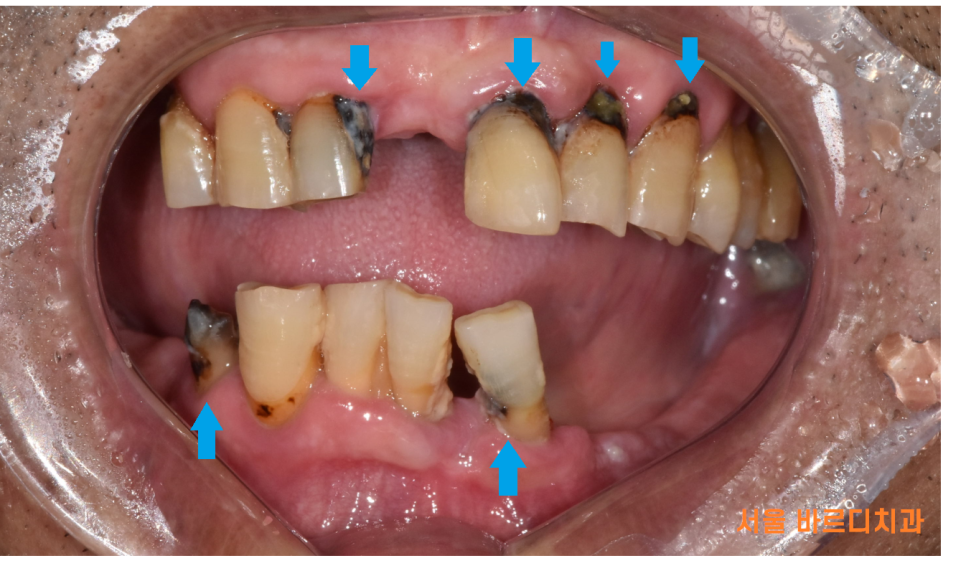

한눈에 보아도 군데군데 썩어있고...

이미 뽑힌 치아도 많았습니다.

치아 상실로 인하여 잇몸 수축이 진행되어 실제보다

나이가 들어보이는 인상을 가지고 계셨는데요.